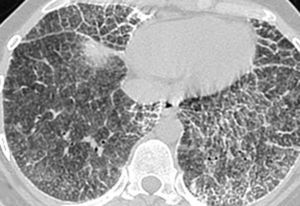

Las imágenes demostraron la presencia de puntiformes y difusas calcificaciones bilaterales, de predominio subpleural, en pleura mediastínica y en los septos interlobulillares. Los segmentos posteriores e inferiores estaban mayoritariamente afectos (fig. 2). También se visualizaron nódulos calcificados a nivel de segmentos anteriores (fig. 2B). El estudio detallado de alta resolución demostró un "patrón en empedrado" o crazzy-paving con marcado engrosamiento de los septos interlobulillares asociado a áreas parcheadas de aumento de la densidad en "vidrio deslustrado" o ground-glass, con mayor afectación de los segmentos posterobasales (figs. 3A y B). A nivel de los lóbulos superiores también se evidencian pequeños quistes subpleurales (fig. 3C).

Fig. 3. Las imágenes tomográficas de alta resolución demuestran la presencia de áreas mal definidas de aumento de densidad en vidrio deslustrado o ground-glass, con moderado engrosamiento de los septos interlobulillares, principalmente en los segmentos anteriores, adoptando en conjunto un "patrón en empedrado" o crazy-paving pattern (A). Secciones inferiores (B) demuestran la mayor afectación de las bases pulmonares. (C) También pueden visualizarse pequeños quistes subpleurales (flechas).

Las imágenes por TCAR15-22 muestran áreas de alta atenuación en "vidrio deslustrado" o ground-glass, con cierta predisposición por las bases pulmonares y segmentos posteriores. Parecen corresponder a cúmulos de microlitos inferiores a 1 mm, aunque también se pueden observar nódulos calcificados mayores de 1 mm15-20. Cuando estas áreas en vidrio deslustrado se asocian a engrosamiento de los septos, adoptan lo que se conoce como "patrón en empedrado" o crazy-paving pattern. Este hallazgo generalmente se ha asociado a patologías tales como la proteinosis alveolar y la neumonía por Pneumocystis carinii, entre otras21,22 y con menor frecuencia a la microlitiasis alveolar.